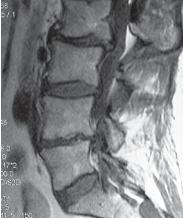

Чтобы вы лучше понимали, как выглядит позвоночник когда в позвоночном сегменте уже нет диска и происходят вышеупомянутые процессы фибротизации и васкуляризации (относящиеся к последней стадии развития дегенеративно-дистрофического процесса), приведу ещё один снимок пациента после многократных хирургических вмешательств.

МРТ № 102

На МРТ № 102 хорошо видно, как после многократных хирургических вмешательств образуется множество послеоперационных рубцов, спаек и других проблем в позвоночнике. То есть, созданы все условия для фибротизации (перерождения ткани диска, образования фиброзных волокон) и васкуляризации (лат. vas — сосуд; формирования новых капилляров, в данном случае при процессе сращивания костной ткани). Всё это способствует сращиванию двух смежных тел позвонков, лишённых диска. В свою очередь это исключает подвижность в данном сегменте, приводит к стенозу фораминальных отверстий (как вы помните, это отверстия, через которые проходят нервные корешки и сосуды). Вдобавок ко всему, послеоперационные спайки и рубцы в спинномозговом канале могут способствовать развитию воспалительных процессов, о которых уже упоминалось выше. Нарушение функциональной способности данного позвоночного сегмента ведёт к ещё большим биомеханическим нарушениям в позвоночнике, соответственно частичной утрате его рессорных свойств, а следовательно, значительному снижению сопротивляемости к разнообразным вертикальным нагрузкам.